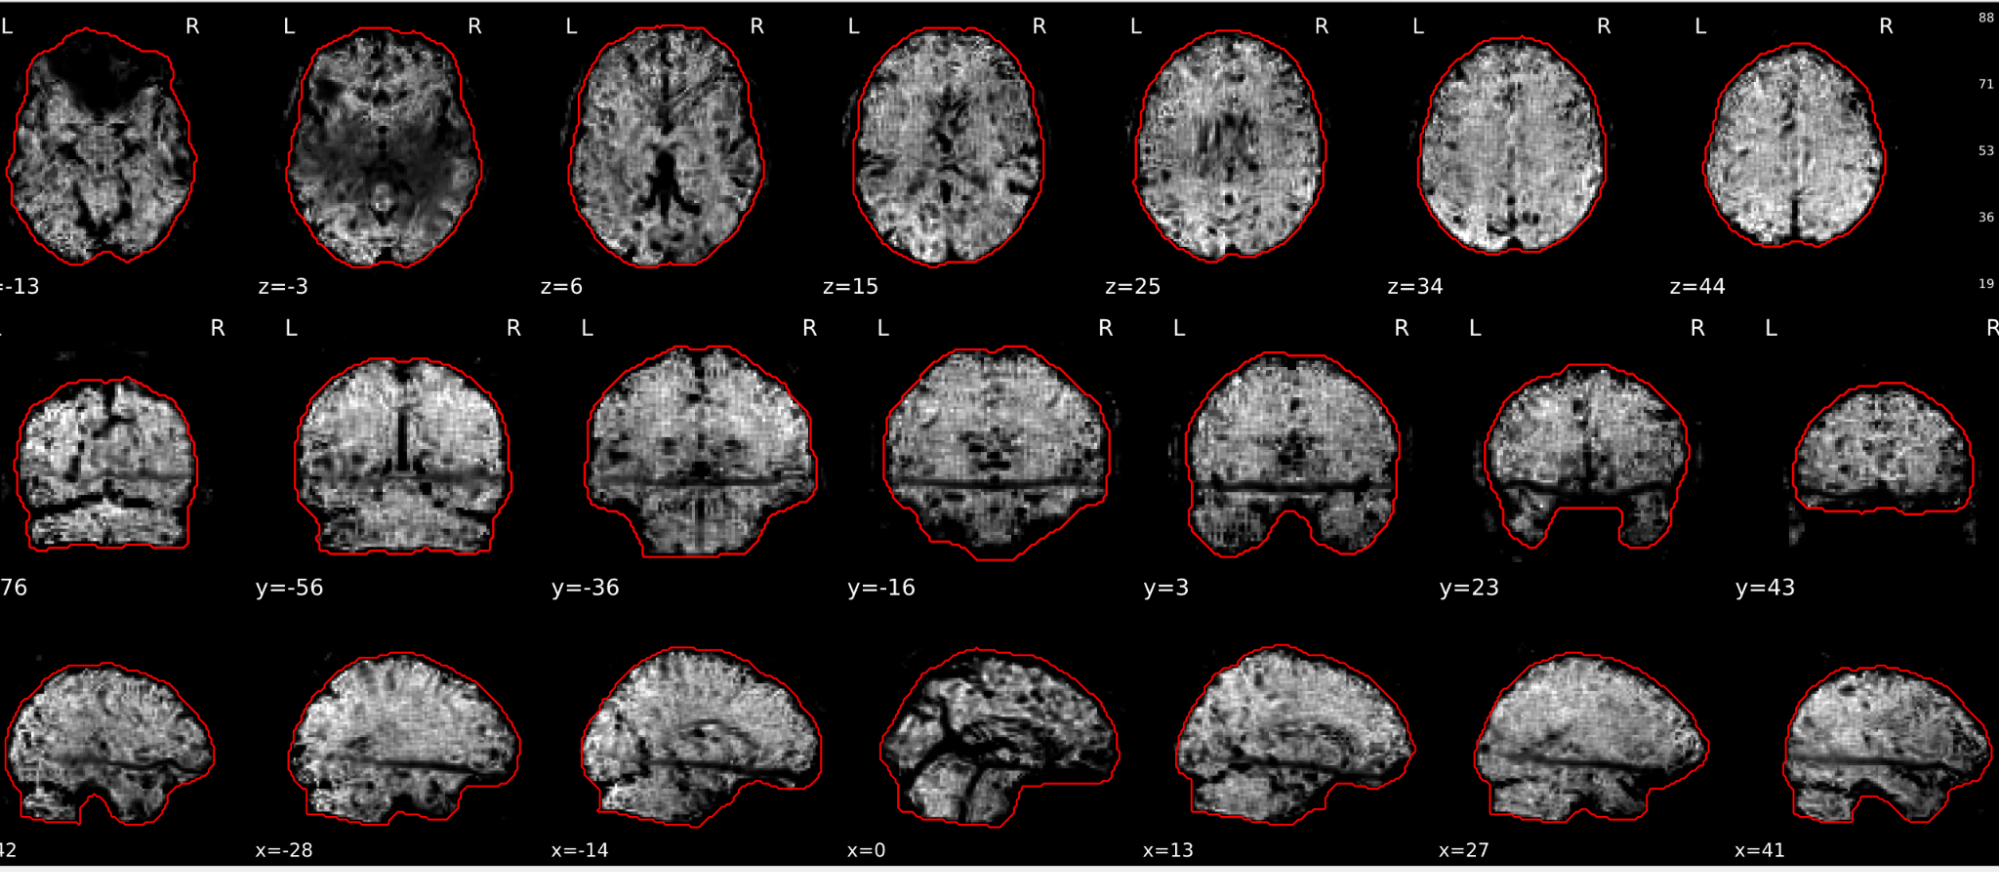

EPI tSNR

In the signal to noise ratio images of the resting state image the desired signal is compared to the amount of background noise. It is important to check all the views (sagittal, coronal, axial) because some artefacts (e.g., stripes) may be evident only in one particular view.

Example of a good subject

- Signal to noise is symmetrically distributed and there is no signal distortion

Example of a bad subject

- Asymmetry

- Potential signal distortion (might represent an artefact)

- Signal drop-out

- Stripes artefact

Clear large artefact (e.g., zebra stripes in example 1) are worth the exclusion of the subject. If you are unsure, check the other quality metrics for that subject to decide whether they should be excluded.

Summary

| good | bad |

|---|---|

| Symmetrical distribution of noise and signal | Asymmetry |

| No disruptions of the signal (no “black patches”) |

Potential signal disruptions (could be related to artefacts) |

| No stripes (sign of high motion) |

Signal drop |

| Stripe artefacts (“zebra” stripes due to motion) |